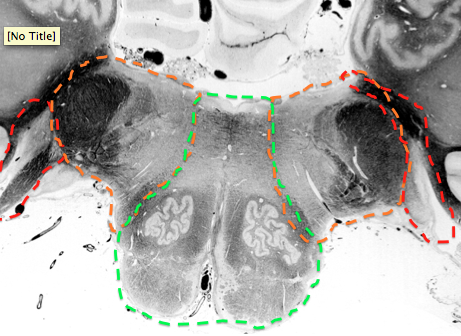

what supplies the dark red?

anterior spinal

what supplies the medial medulla?

anterior spinal a.

what supplies the top lateral portion of the open medulla

pica

Blue?

top of Caudal medulla

Posterior spinal a.

Green?

Vertebral a.

lateral protion from middle to rostral medulla (orange below)

Rostral Lateral medulla

includes spinal trigem, solitary nucleus, ALS, interior cerebellar peduncle

What supplies top of medulla until the fasciuli go away?

posterior spinal artery

includes gracile nulcueus, cuneate fasiculus and nucleus

What supplies olivary complex in the caudal to middle medulla?

vertebral

what supplies rostral medial medulla? until when?

paramedian branches of basilar. once you get to the mouse ears

when does the posterior spinal disappear from the medulla?

by the time its only cuneate nucleus

when does the anterior spinal replaced? what replaces it to feed middle rostral medulla?

when CN 8 comes in

replaced by paramedian branches of basilar

when does AICA first appear?

in rostral medulla when CN 8 comes in

in the medulla it just supples dorsal cochlear nucleus and the CN 8